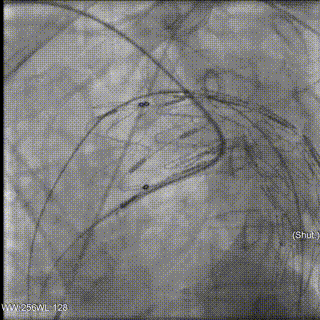

手术方案:TEVAR+右侧和左侧锁骨下烟囱。

手术结果良好,无任何内漏。